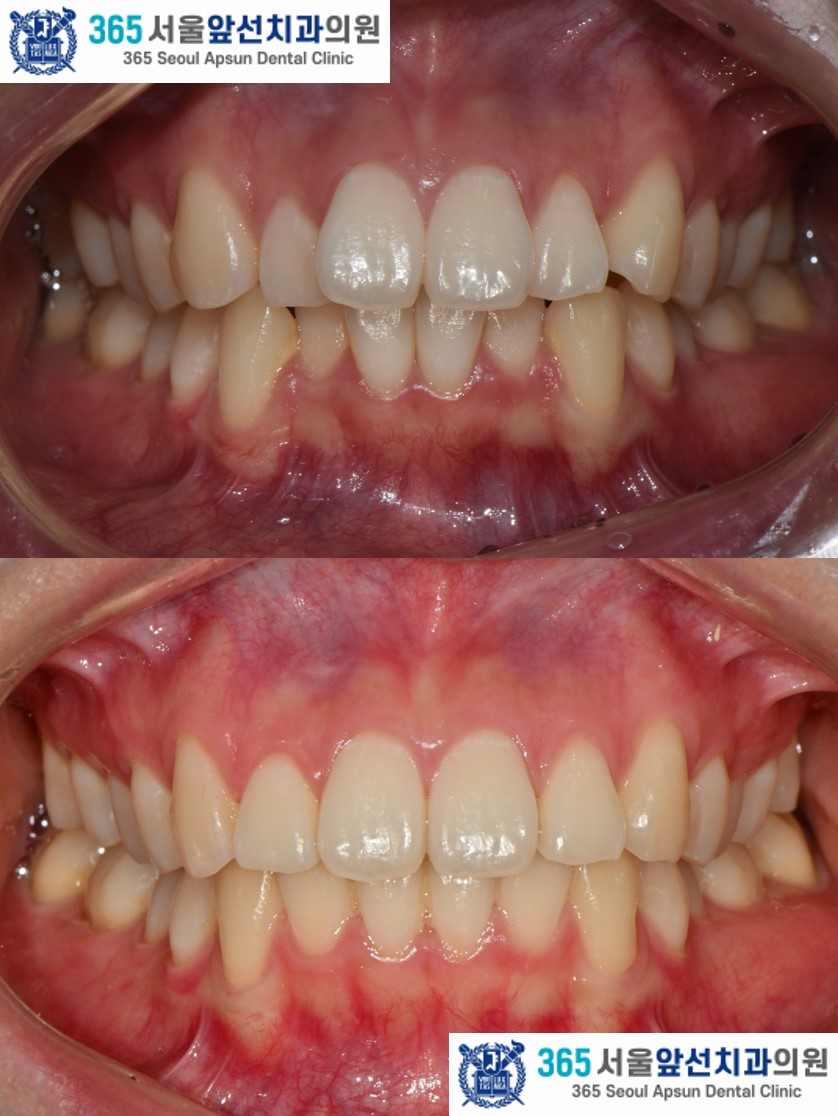

(그림1) 촬영일자 2025.02.25. / 2025.11.06.

치료 후의 모습입니다. 아랫니 치열은 약 5개월, 윗니 치열은 약 7개월의 치료기간이 소요되었습니다. 앞니의 치열이 가지런하게 배열되어 환자분도 만족하셨습니다. 미소 시 자연스럽고 단정한 인상으로 변화하였습니다. 앞니 부분 교정 증례의 치료기간은 4-9개월 사이로 정도에 따라 상이합니다. 부분 교정 관심 있으신 환자분들께서는 365서울앞선치과로 내원하셔서 교정 진단 받아보시길 바랍니다. 감사합니다!